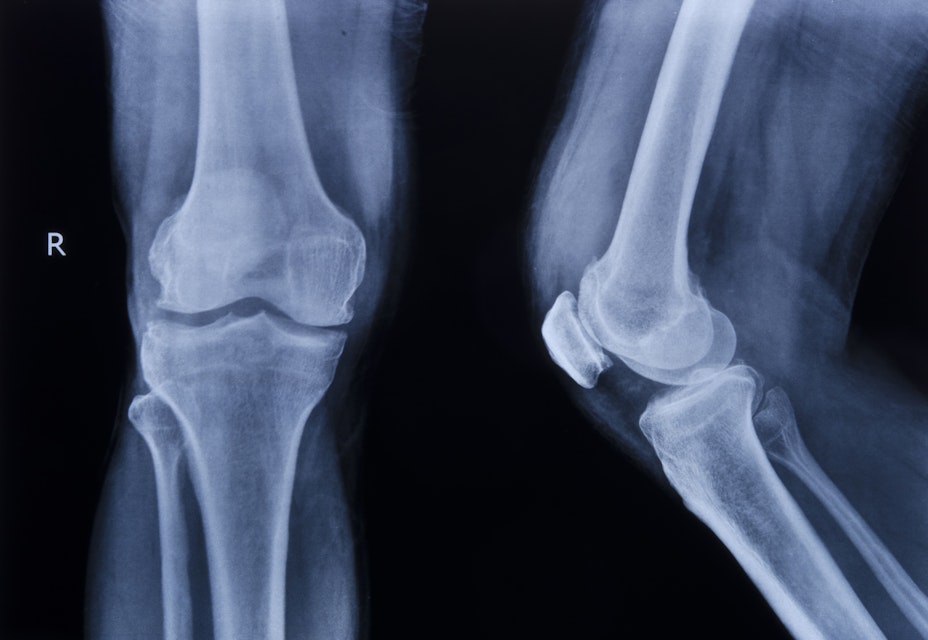

I januari månads expertkommentar i migrationsrätt skriver Viktoria Nyström om rättsosäkerheten kring de kraftigt kritiserade medicinska åldersbedömningarna i asylärenden. ”Det vi ser nu är ingenting annat än en rättsskandal” skriver Nyström, som menar att åldersutredningarna i deras nuvarande form genast bör stoppas.